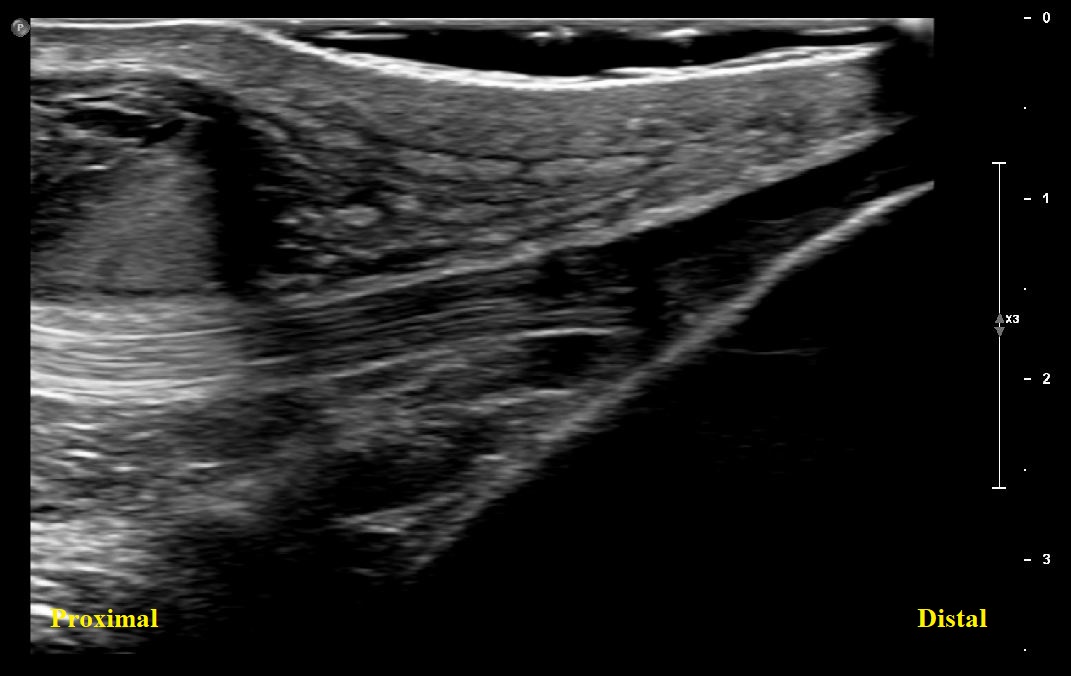

Long axis view of distal patellar tendon with overlying bursal distension

Long axis view of right distal patellar tendon. There is partial visualization of a distended prepatellar bursa with complex fluid. Distal Patellar tendon is intact. There is no superficial or deep infrapatellar bursal distension/bursitis